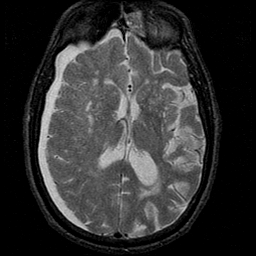

Subdural Hygroma,overlay -- Slice #26

[Home][Help][Clinical] Slice 26